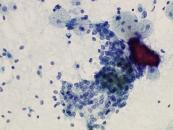

第38回日本臨床細胞学会九州連合会学会(熊本)スライドカンファレンス症例1

種別:婦人科

出題:仲田 典弘 中頭病院病理診断科

| 年齢 | 70代 | 性別 | 女性 |

| 採取部位 | 右卵巣 | 採取方法 | 捺印 |

既往歴:右乳癌(7年前)、右卵管妊娠(40年前)。

現病歴:半年前から腹部膨満感あり受診。造影CTで嚢胞性卵巣腫瘍が疑われ手術となった。

| 正解 | 5.ブレンナー腫瘍 |

▼選択肢及び投票結果

| 1.奇形腫 | 10件 | (9.6%) | |

| 2.明細胞癌 | 34件 | (32.7%) | |

| 3.類内膜癌 | 7件 | (6.7%) | |

| 4.顆粒膜細胞腫 | 12件 | (11.5%) | |

| 5.ブレンナー腫瘍 | 41件 | (39.4%) | |

| 投票総数 | 104件 | (100%) |